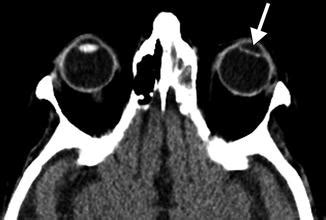

So, what exactly is pseudophakia ? The term itself breaks down like this: “pseudo” means false or artificial, and “phakia” refers to the presence of a lens in the eye. Put them together, and you’ve got pseudophakia : the state of having an artificial lens. This artificial lens, known as an intraocular lens (IOL), is implanted in the eye to replace the natural lens that has become cloudy due to cataracts. Cataracts, by the way, are a common age-related condition where the natural lens of the eye becomes opaque, leading to blurred vision. Think of it like looking through a foggy window – that’s what cataracts do to your vision. Pseudophakia is the solution to restore clear vision once the natural lens is no longer doing its job.

The whole process revolves around cataract surgery, one of the most common and safest surgeries performed worldwide. During this surgery, the clouded natural lens is removed, and the IOL is carefully inserted in its place. The IOL is designed to perform the same function as the natural lens, which is to focus light onto the retina, allowing you to see clearly. The beauty of pseudophakia is that it can significantly improve your vision, often to the point where you no longer need glasses or contacts for distance vision. However, many people still require reading glasses for close-up tasks.